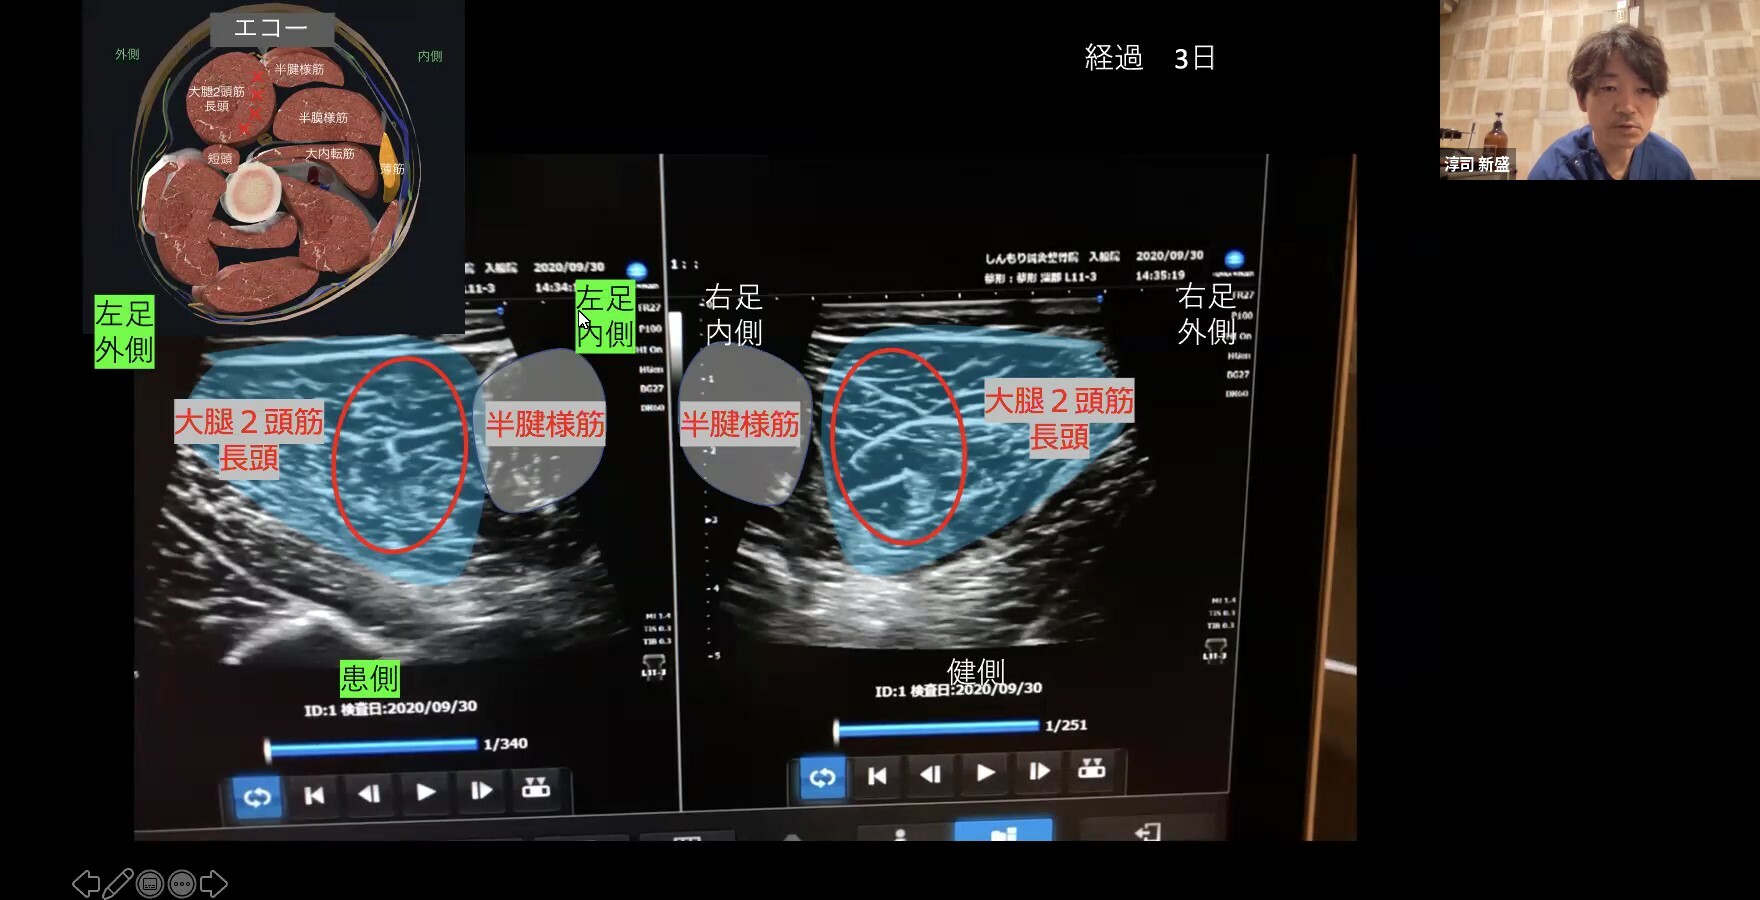

講演テーマは「市場価値あるトレーナーになる為にやってきた事 ~ハムストリングス肉離れのトレーナーとしての介入~」で、学生、一般参加者を合わせて約115名の方にご参加いただきました。

価値あるトレーナーになるために、学生の内にやるべきことやトレーナーとしての行動、そしてハムストリングス肉離れの評価方法としてのエコー(超音波)の活用法などを詳しくご講演いただきました。約50分のご講演の後の質疑応答が約90分に及ぶ異例のセミナーとなりましたが、夜遅くまで学生の質問に対してご丁寧にこたえていただきました。

”肉離れについて理解できた。再発の20%について自分も考えてみたい。そしてエコーが判断において重要なものだということがわかり、エコーについて自分はまだ内容が深掘りできていないので今後役に立てたらいいなと思う。この時間、とても内容の濃いものになった。”

”エコーによる評価が広がって、復帰基準など定量化できれば肉離れ再発の予防に大きく繋がるのではないかと感じました。将来柔道整復師として活動する中でエコーでの評価は非常に重要となると思うので学生のうちに積極的に使用していきたいと感じました。”